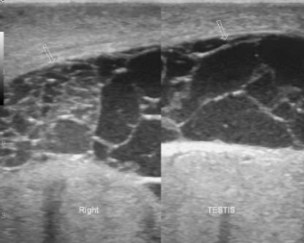

normal measurement of testes

3-5 x 2-4 x 3 cm

what component of the testis makes them appear as echogenic

seminiferous tubules

the testis are covered by the...

tunica albuginea

mediastinum testis

posterior aspect of tunica albuginea that forms vertical septum